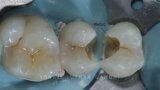

Management of proximal posterior lesions- A case report